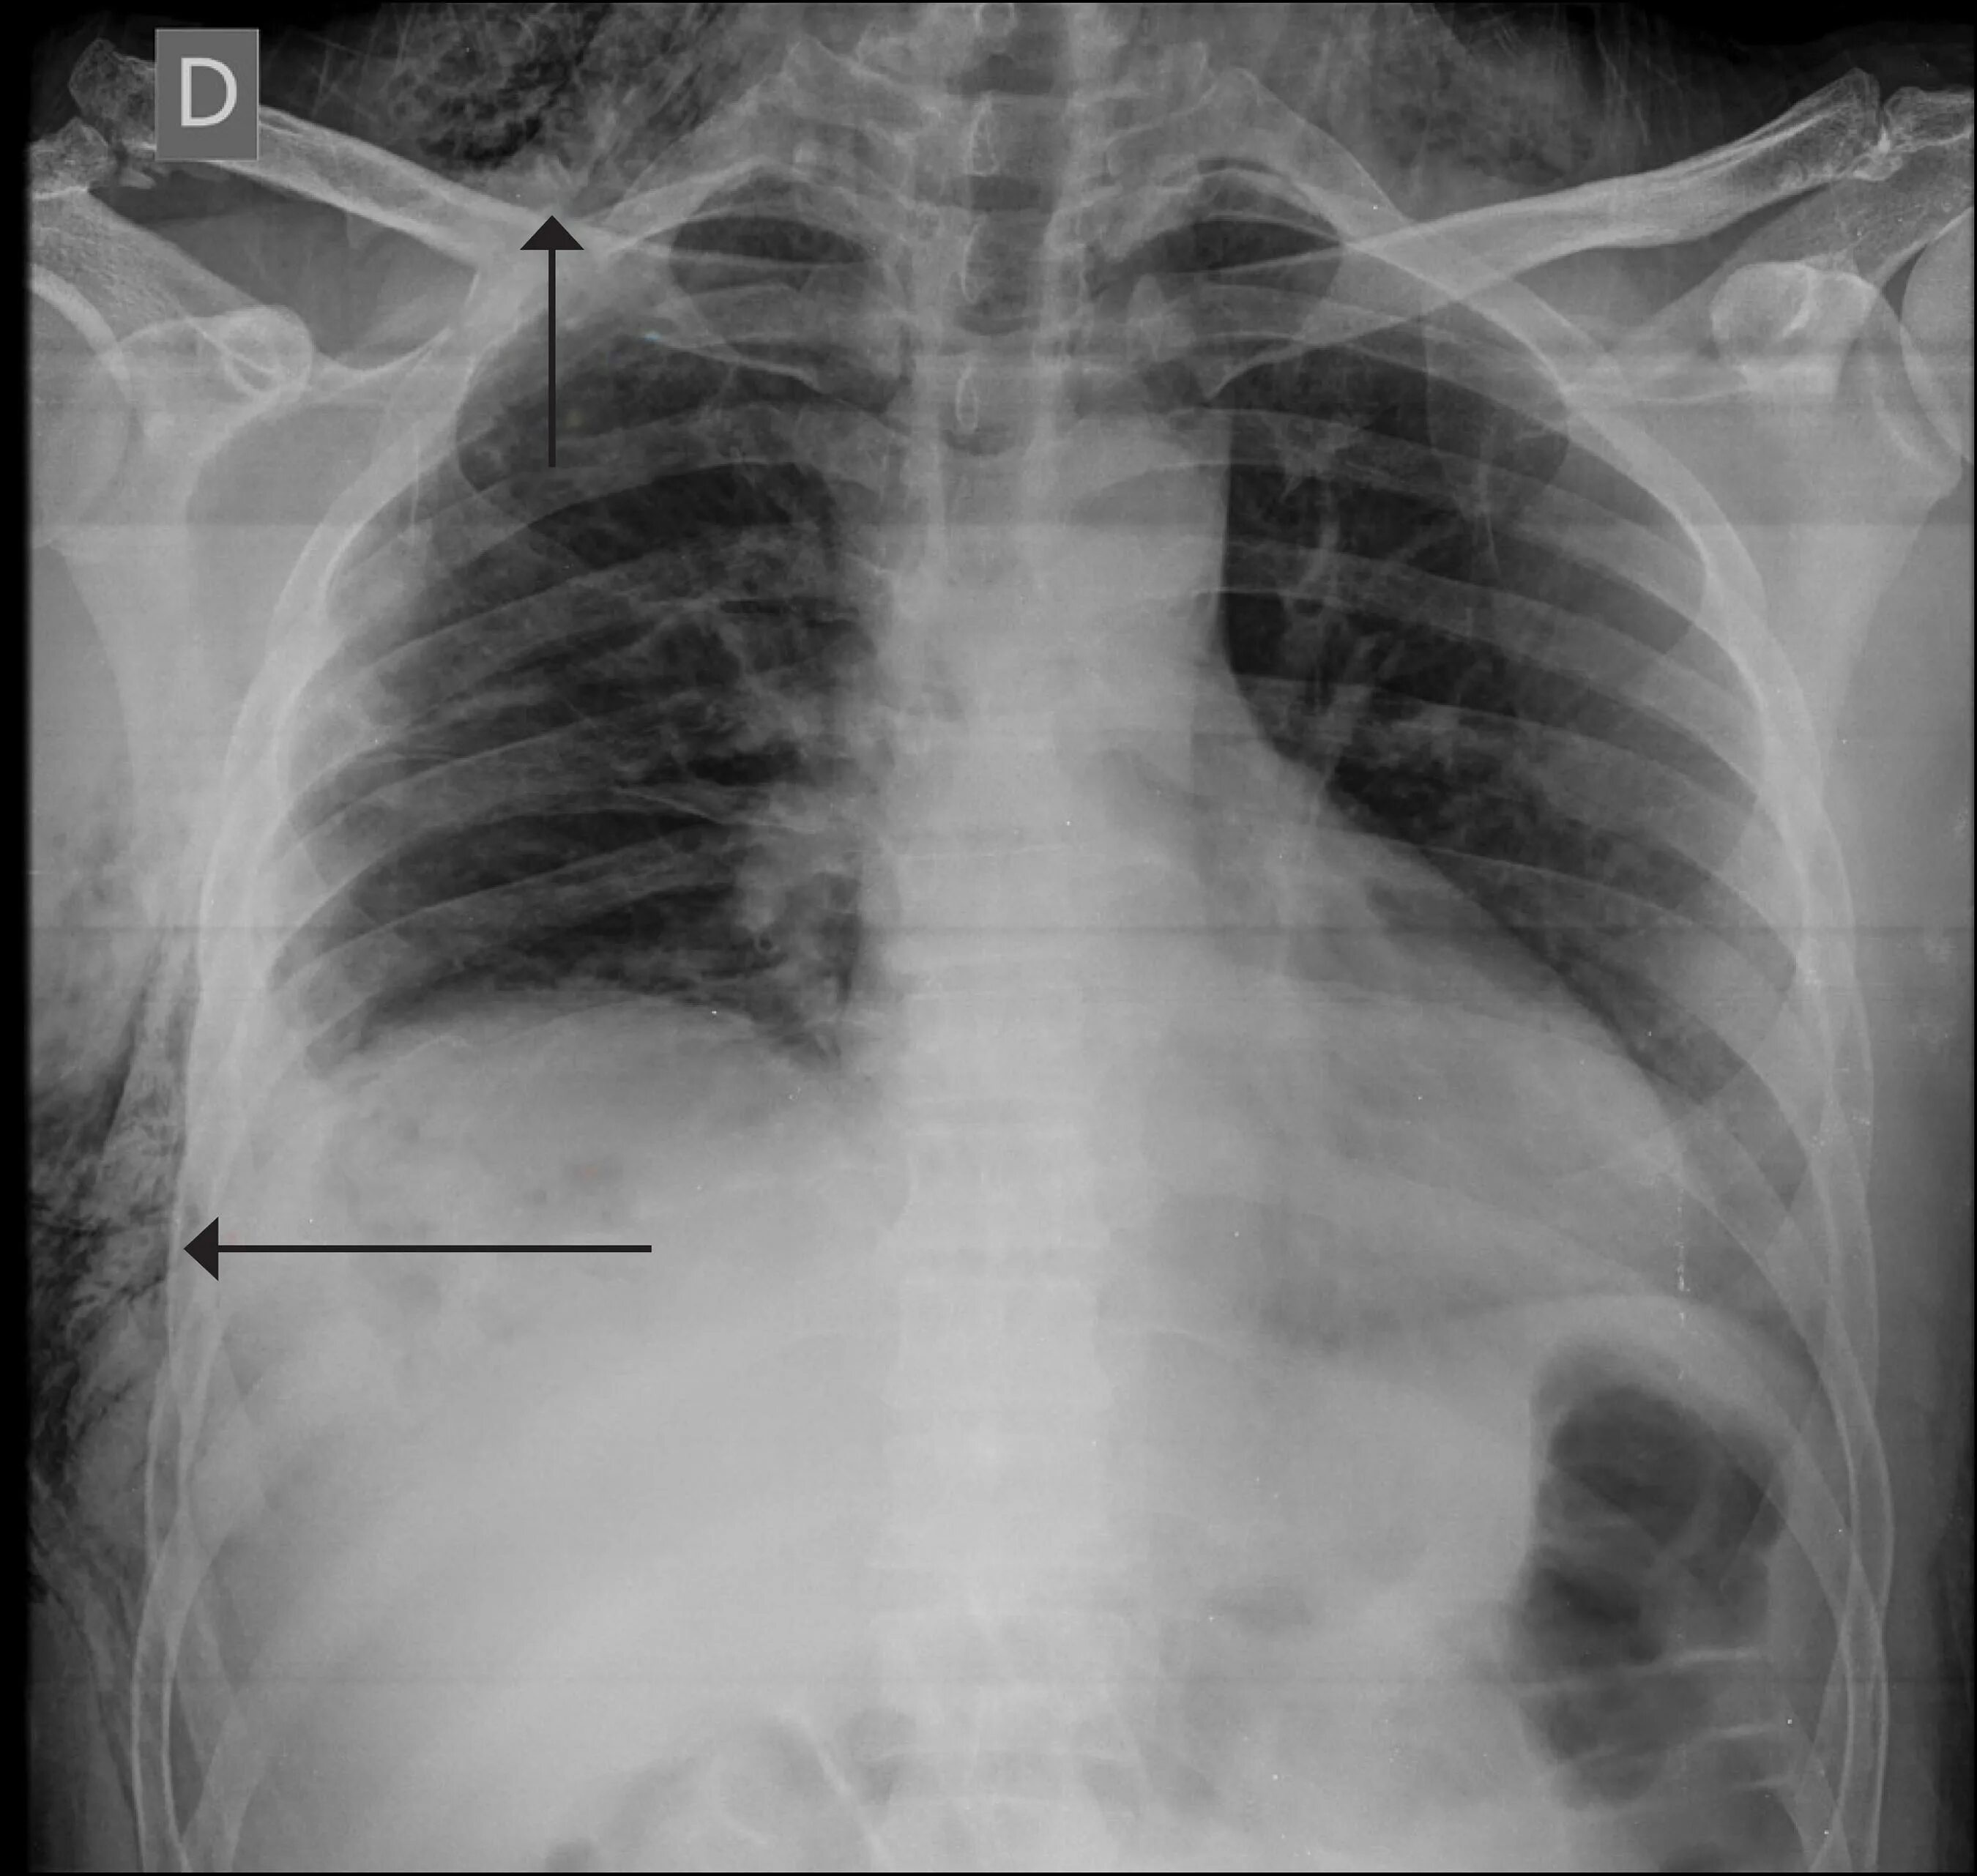

Эмфизема мягких